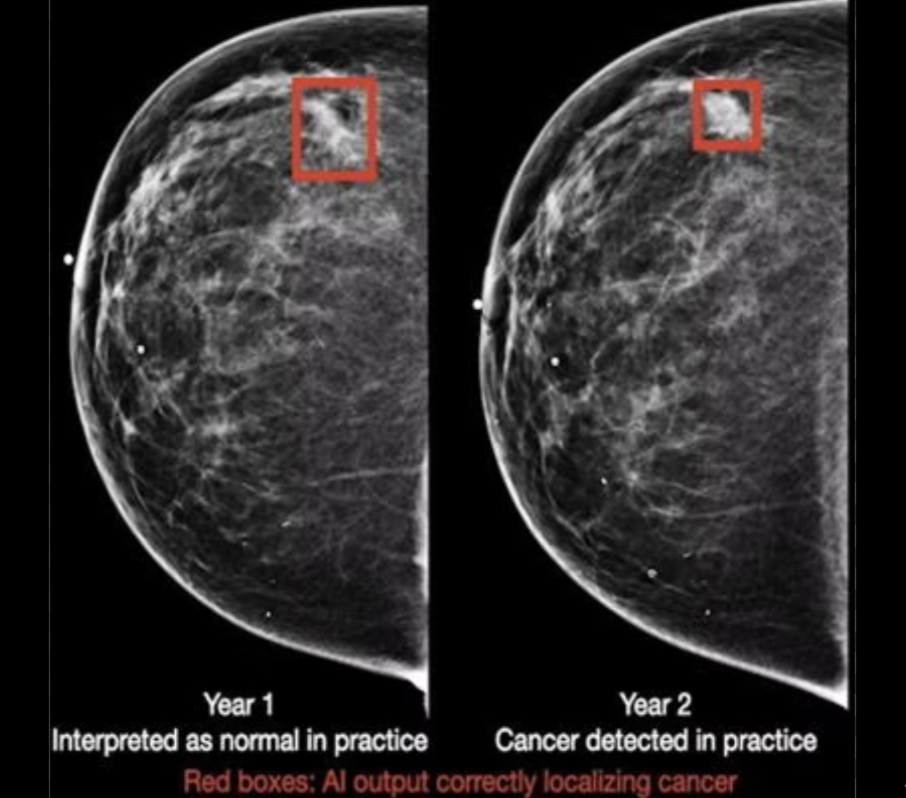

With the rise of 3D mammograms, radiologists must view a substantially larger volume of images. AI can assist this analysis with its potential to find cancers before they become visible to even the trained eye.